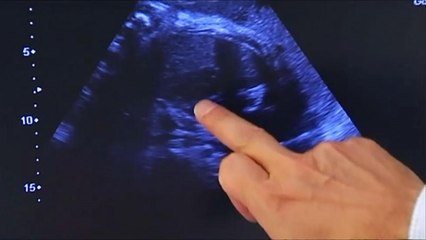

O Parlamento chileno aprovou nesta quinta-feira o aborto em três casos especiais. Uma decisão que causou grande polêmica no país sul-americano.